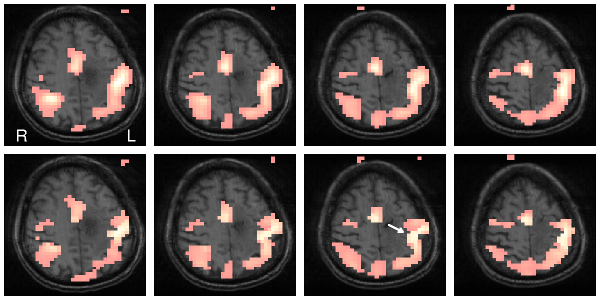

Figure 1: Upper row: Signal detection in a fMRI experiment using non-adaptive Gaussian filter in 4 subsequent slices.

Lower row: Signal detection using a structure adaptive procedure. Shape of grey matter can be seen much better (see arrow).